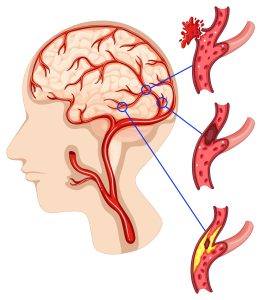

Minor stroke atau Transient Ischemic Attack (TIA) sering dianggap ringan kerana simptomnya bersifat sementara. Namun hakikatnya, ia adalah amaran awal bahawa risiko strok penuh boleh berlaku pada masa hadapan. Oleh itu, memahami cara merawat minor stroke dengan betul dan berkesan adalah langkah penting untuk mencegah komplikasi yang lebih serius.

Minor stroke berlaku apabila aliran darah ke otak terganggu buat sementara waktu, menyebabkan simptom seperti:

Walaupun simptom ini boleh hilang dalam masa beberapa jam atau hari, pesakit tidak boleh mengabaikannya. Tanpa rawatan yang betul, risiko untuk mendapat strok sebenar adalah sangat tinggi. Oleh itu, pemilihan cara merawat minor stroke yang menyeluruh amat diperlukan.

Rawatan awal bagi minor stroke amat penting kerana ia bukan sahaja membantu memulihkan fungsi tubuh yang terjejas, malah berperanan besar dalam mencegah kerosakan saraf jangka panjang serta mengurangkan risiko berlakunya strok penuh pada masa hadapan. Ramai pesakit tersilap anggapan bahawa simptom yang hilang dengan cepat tidak memerlukan rawatan lanjut, sedangkan hakikatnya minor stroke adalah tanda amaran awal kepada masalah saluran darah otak yang lebih serius.

Pendekatan cara merawat minor stroke yang berkesan perlu dilakukan seawal mungkin bagi menyokong proses pemulihan otak dan sistem saraf. Antara fokus utama rawatan awal termasuklah melancarkan aliran darah ke otak supaya bekalan oksigen dan nutrien dapat disalurkan dengan optimum, sekali gus mengurangkan tekanan pada sel-sel otak yang terjejas.

Selain itu, rawatan awal juga membantu memulihkan fungsi saraf yang terganggu akibat gangguan aliran darah. Ini penting bagi mengurangkan simptom seperti kebas, kelemahan anggota badan, gangguan pertuturan dan masalah keseimbangan. Pada masa yang sama, rawatan yang tepat mampu mengurangkan keradangan dalam sistem vaskular, yang merupakan salah satu faktor utama penyumbang kepada kerosakan saraf berpanjangan.